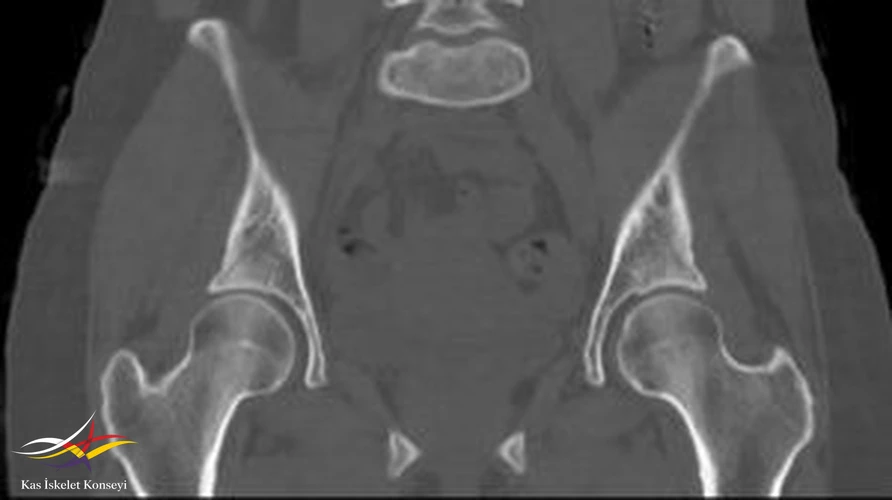

İncelemeler: Kalça MRG ve BT incelemelerinde sol femur trokanter major bölgesinde kemik iliği ödemi, bilateral şüpheli trokanterik bölge fraktür hattı, trokanterik bursit ile uyumlu görünüm saptandı.

Resim 4. BT incelemesinde sol tokanter majörde şüpheli fraktür hattı izlenmekte.